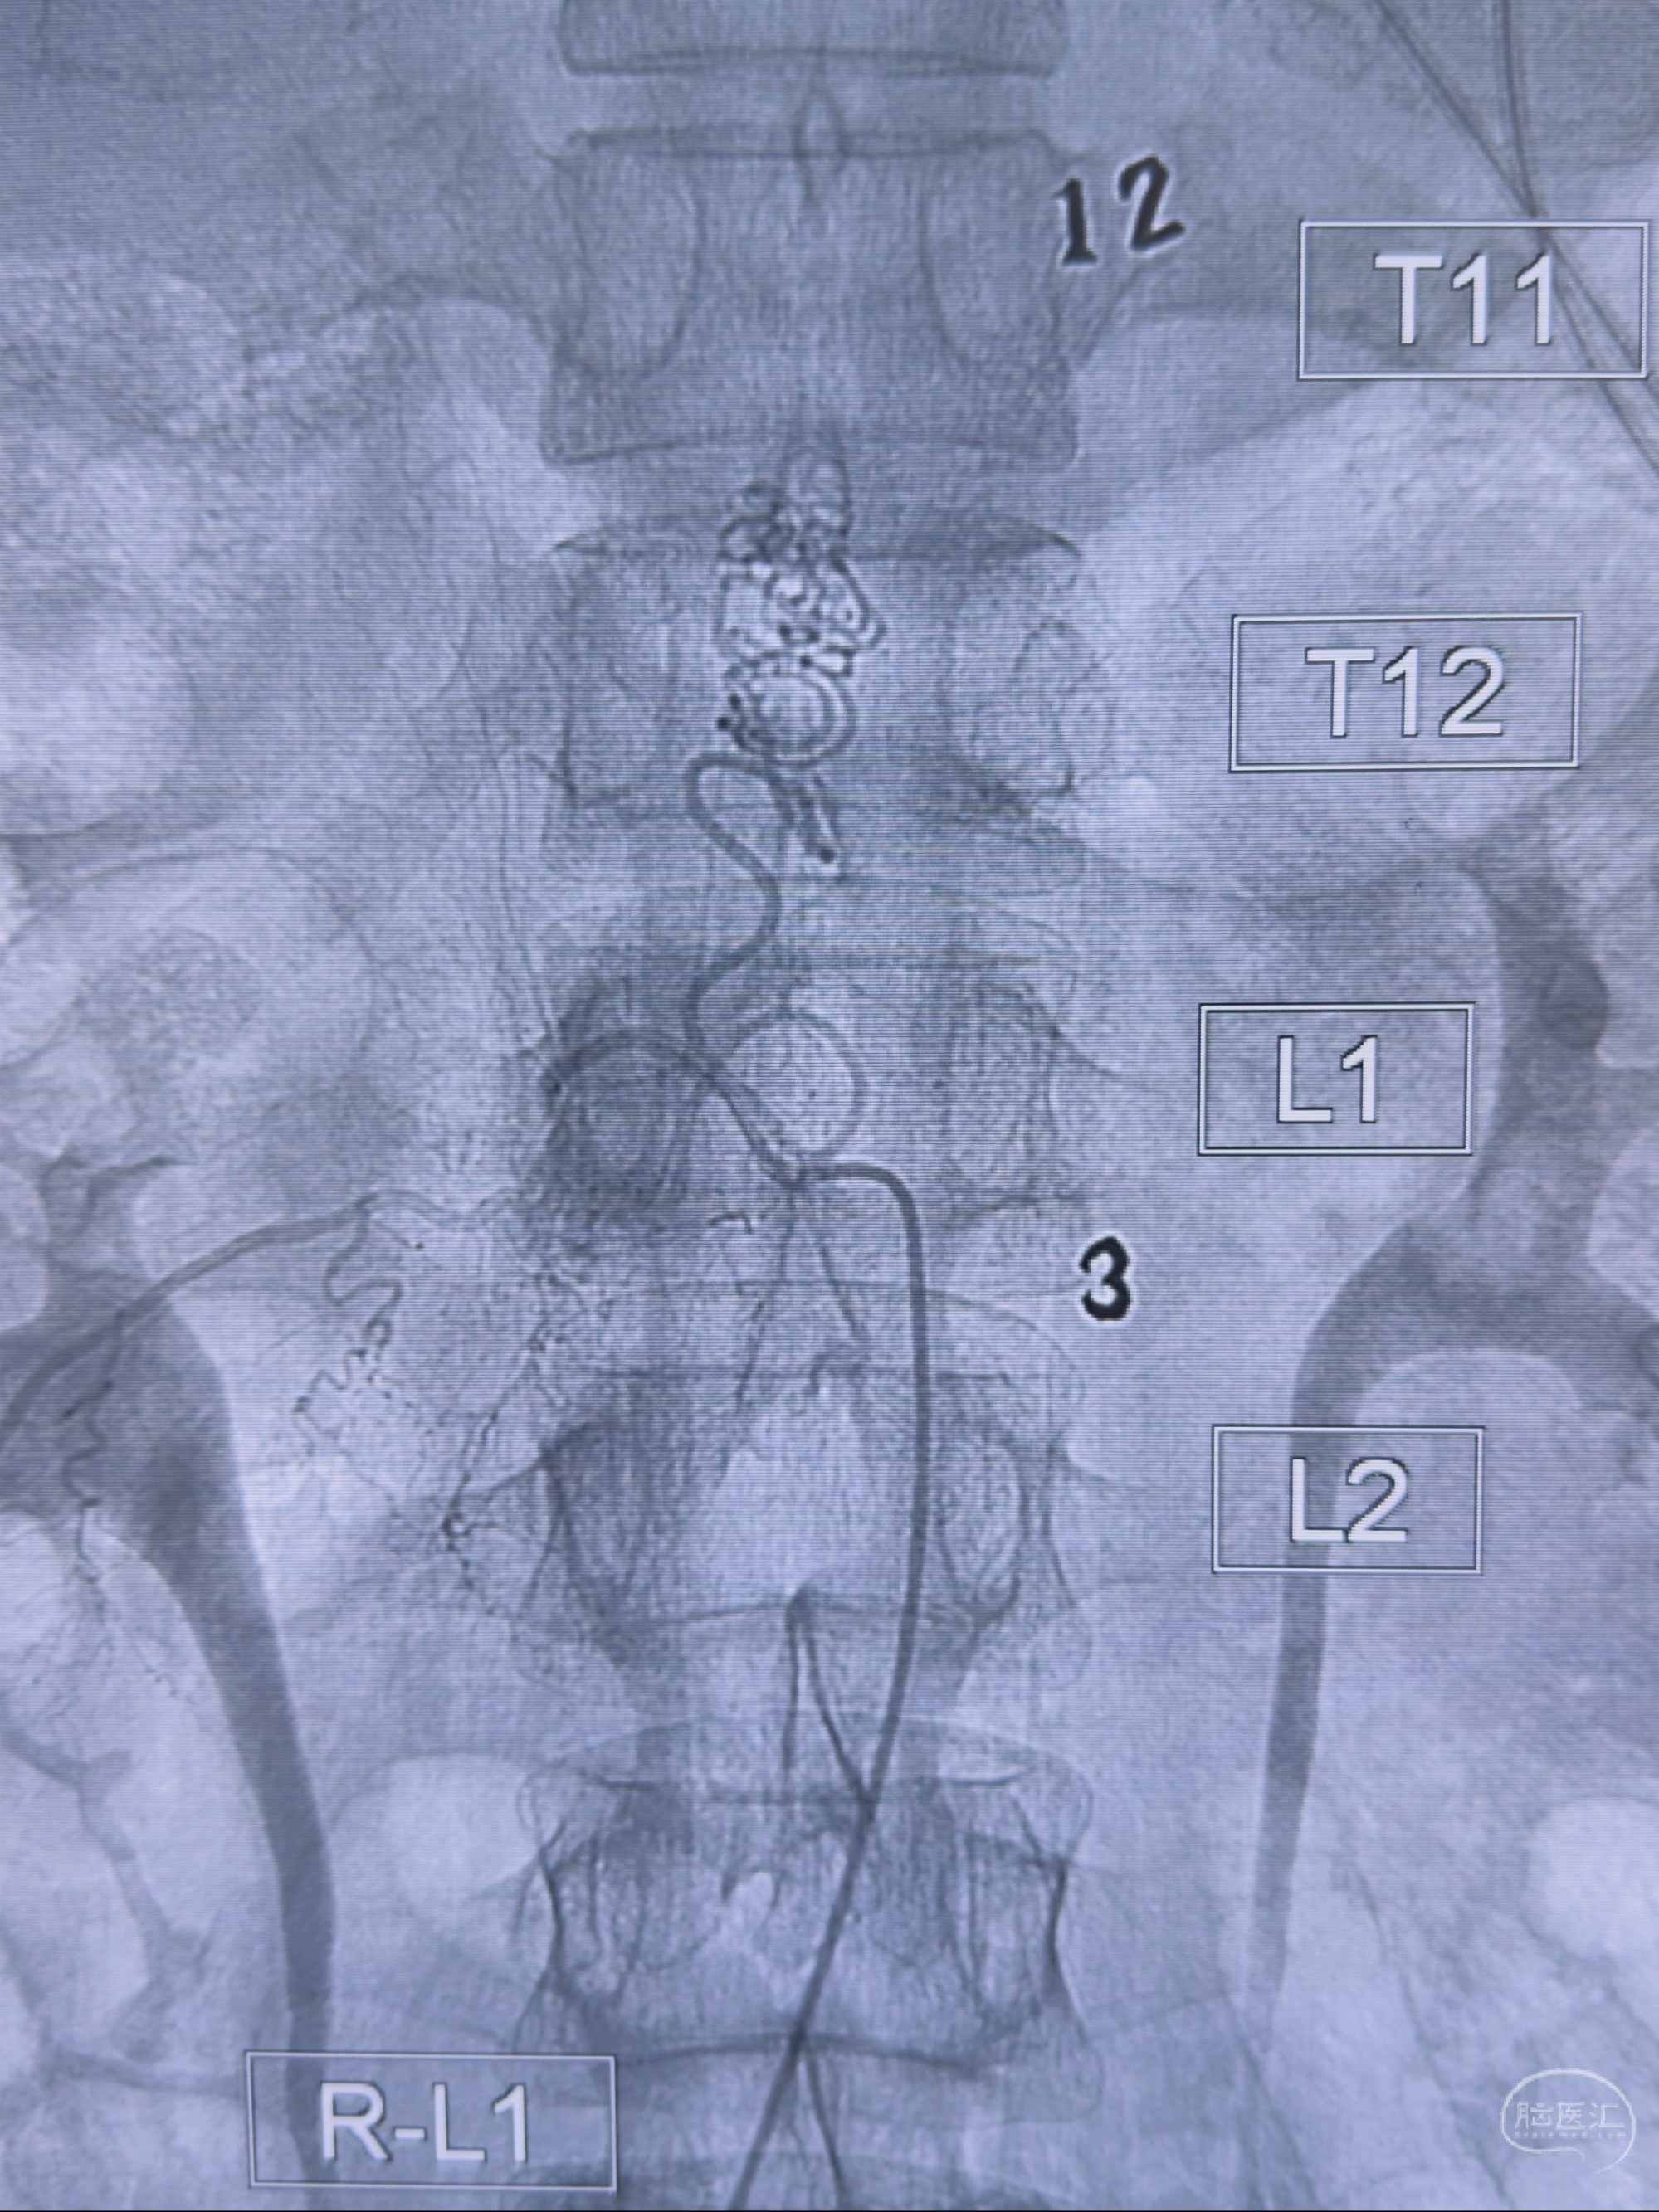

2023-10-13DSA:右侧L1水平硬脊膜动静脉瘘,供血动脉为右侧L1,附近动脉未见明确吻合供血,供血动脉处可见脊髓前动脉发出